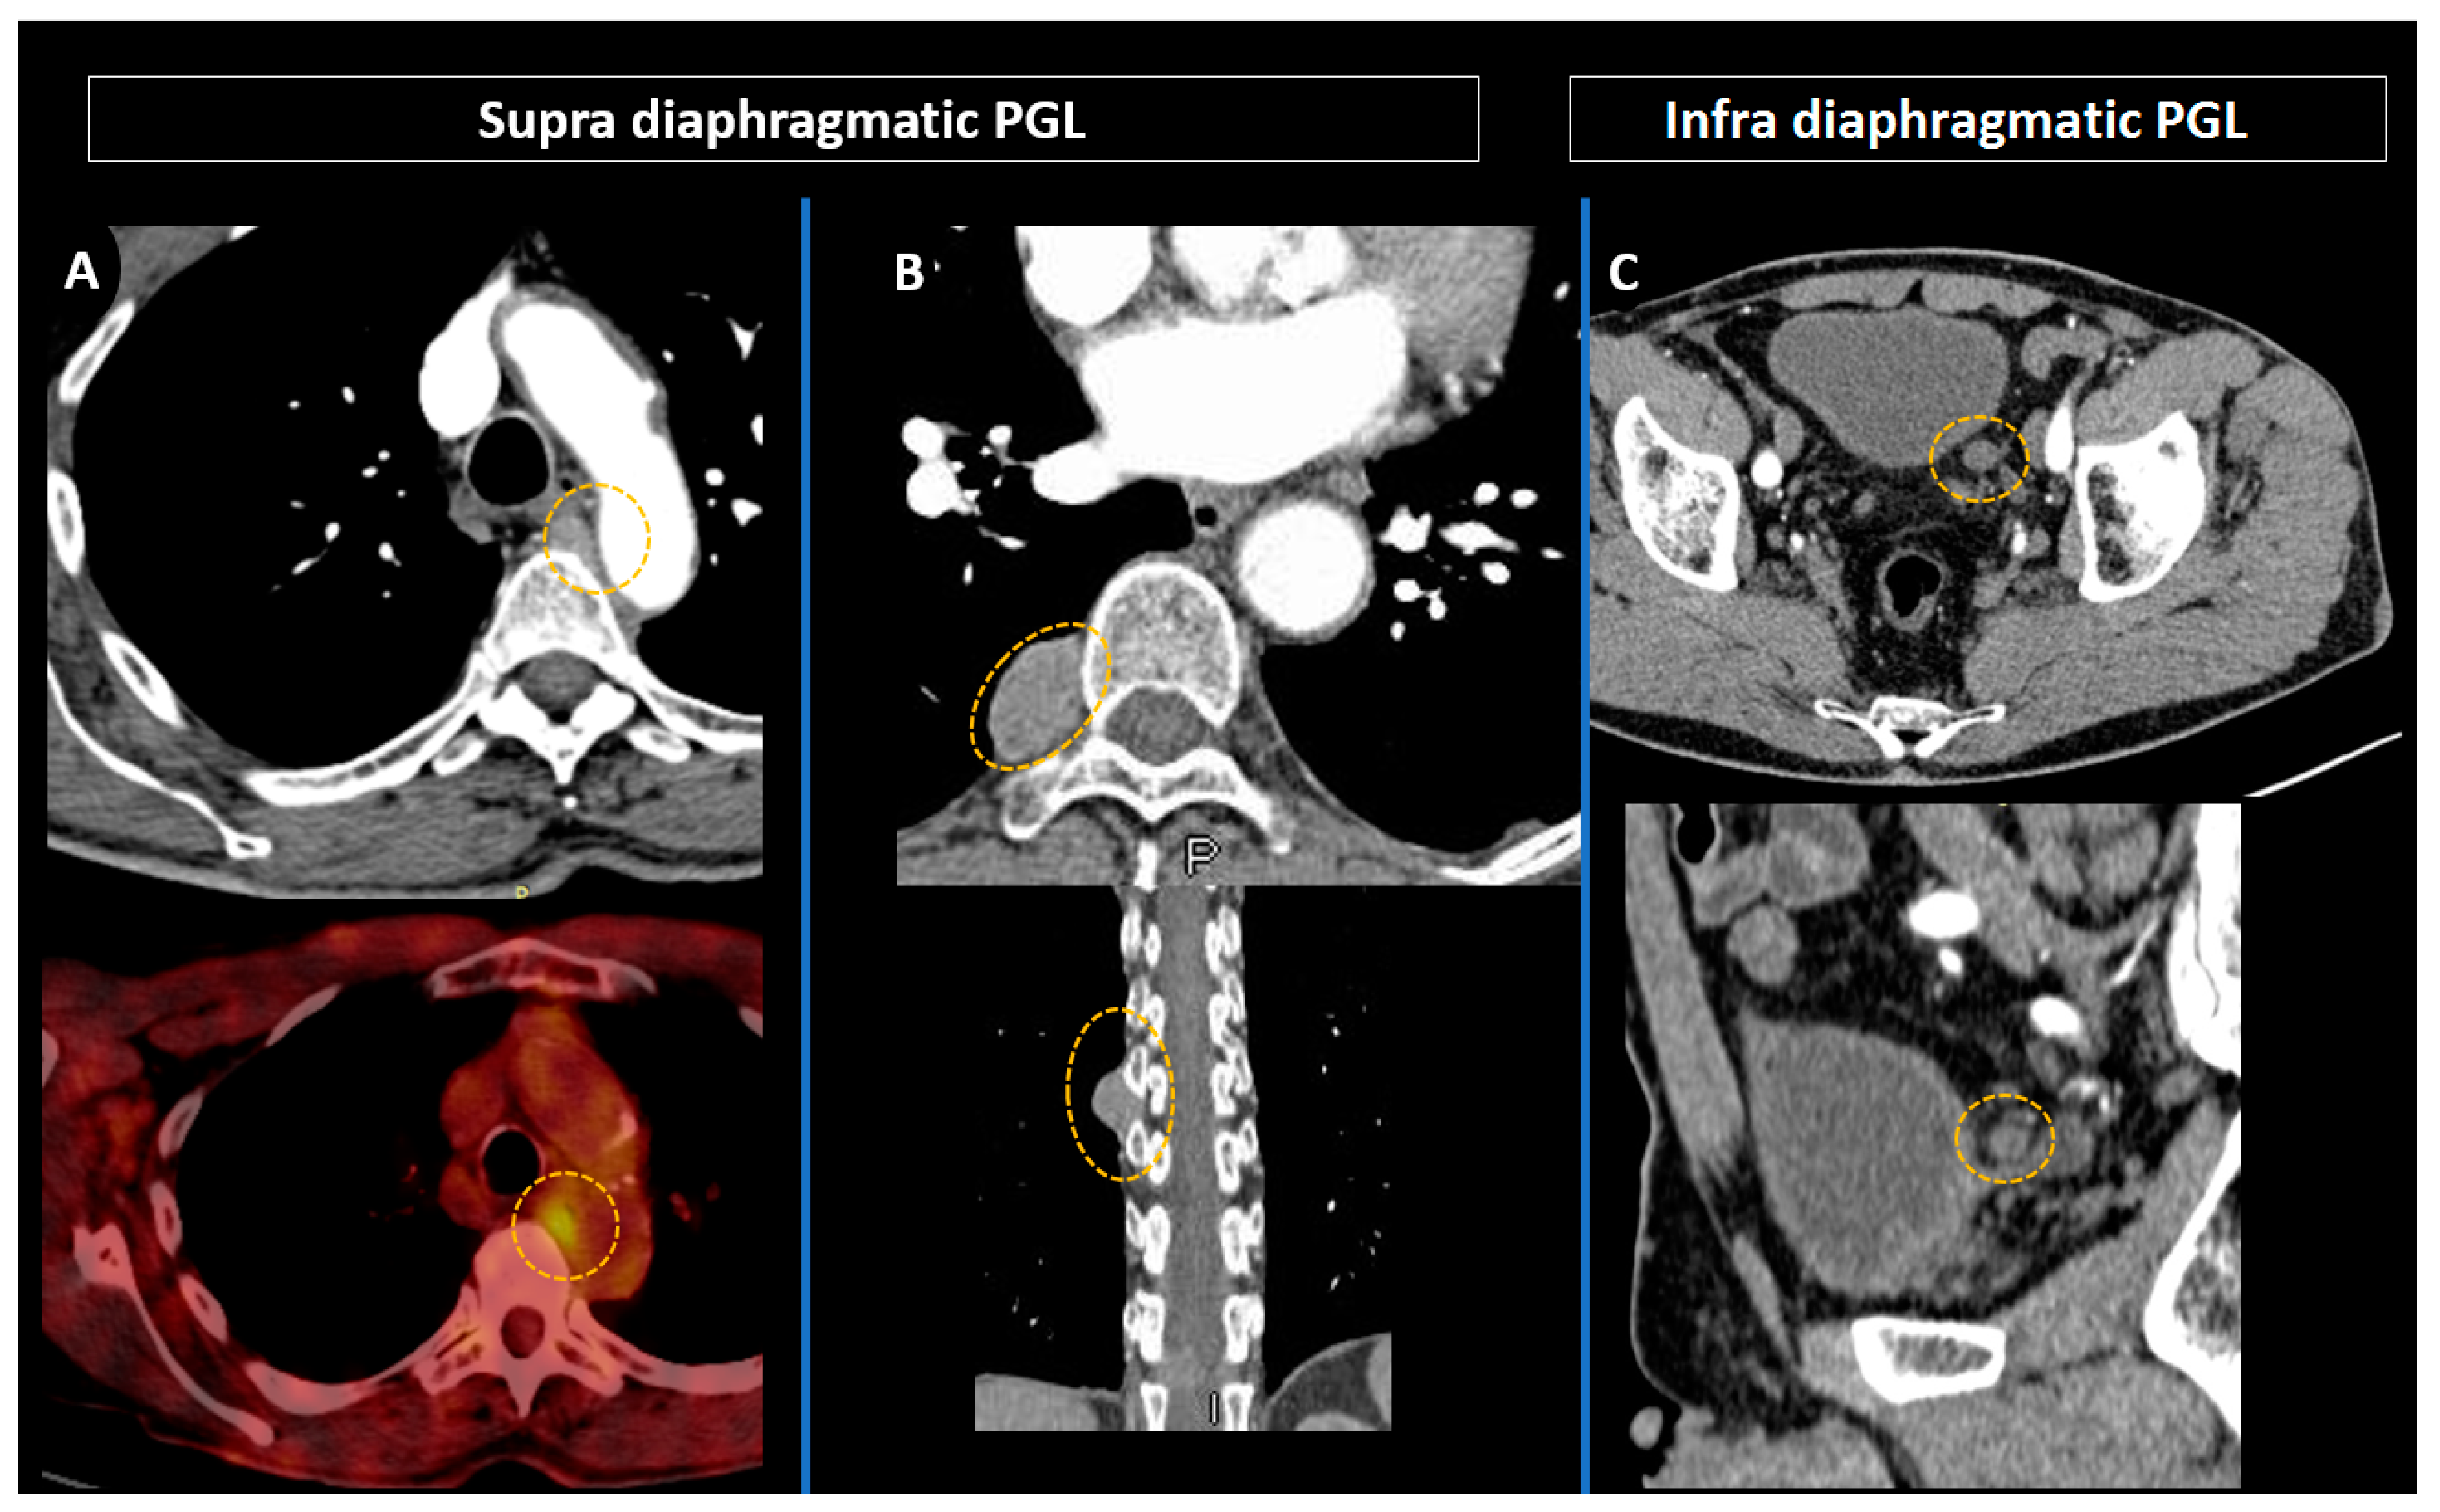

4.3. Positron Emission Tomography with Computed Tomography Using Somatostatin Analogues

4.4. Current Guidelines for Molecular Imaging in Diagnosis and Staging of PPGLs